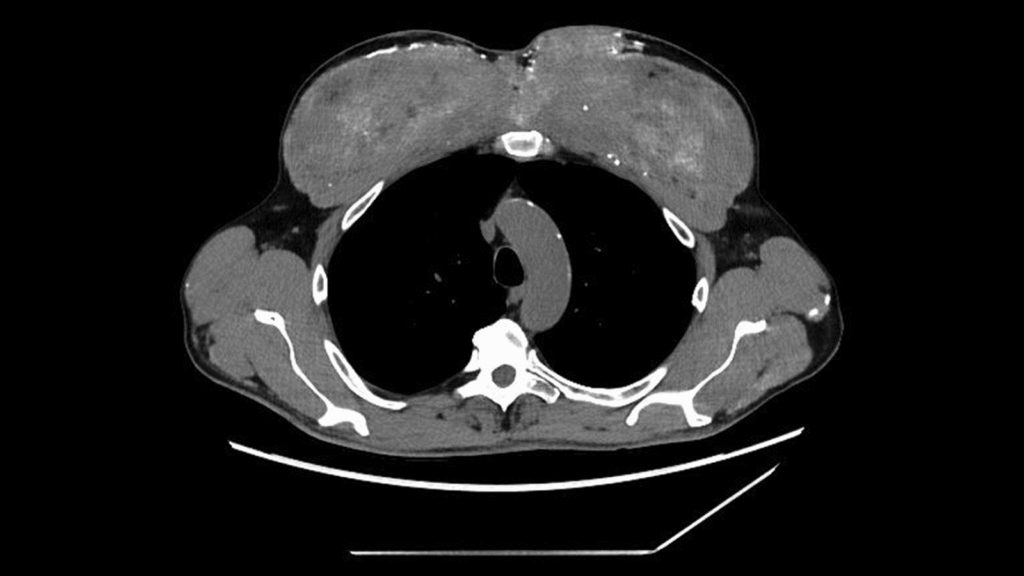

The man’s condition was generally stable, but a physical examination showed significant changes in his upper arm and chest muscles, consistent with the irregularities seen in the scan. Doctors then reviewed the patient’s medical history, and the patient revealed important details. According to the patient’s report, he began receiving “unknown intramuscular injections (possibly containing testosterone)” about 30 years ago to enlarge the muscles in his chest and upper arms.

Diagnosis: Under a microscope, the muscles were filled with a silicone-like oil-based substance and surrounded by dense calcium deposits. The researchers speculated that the man’s previous intramuscular injections likely contained synthol, a substance made primarily of oil that causes the muscles to visually “plump up,” essentially inflating them like water balloons.

In this case, synthol caused a persistent foreign body reaction. In other words, the body essentially reacts to substances that cannot be broken down. Over time, this reaction causes scarring and calcification, leading to the accumulation of large amounts of calcium within the muscles. And eventually, that calcium entered his bloodstream.